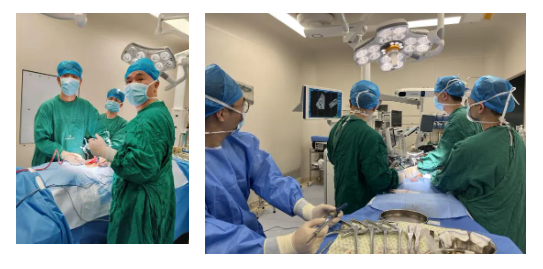

近日,广东医科大学附属医院脊柱微创外科在技术探索与临床创新之路上再次迈出坚实的步伐,在副院长林颢教授、科室主任魏波的带领下,胡资兵主任团队成功完成粤西首例“C臂导航下S2AI螺钉置入术”。

患者感染病灶位于腰5、骶1,骶1骨质破坏,置入椎弓根钉强度欠佳,容易松动、拔钉,导致内固定失败。传统使用髂骨螺钉替代骶1椎弓根钉,但髂骨螺钉存在钉尾突兀刺激皮肤、与近端腰椎椎弓根钉不在同一纵线、连接困难等缺点。鉴于脊柱微创外科团队过去已在美敦力S7系统辅助下成功完成多例精准导航脊柱外科手术,胡资兵教授团队在征得患者及家属同意后,决定采用“C臂导航下经后路腰5、骶1感染病灶清除、椎管减压、S2AI螺钉、腰椎椎弓根钉棒内固定术”来解决此难题。

S2AI为经骶2骶髂螺钉,置入后与近端腰椎椎弓根钉保持在同一纵线上,连接方便,而且不存在钉尾突兀刺激皮肤的问题,近年来已成为备受推崇的腰骶固定方式,但一直以来S2AI螺钉的置入都极具挑战性。此例患者软组织丰厚,腰骶段暴露困难,更加大了置钉难度。C臂导航对S2AI置入的准确度和安全性具有非常明显的优势,大大降低了以往仅仅根据术者经验完成手术的风险,实现了数字化、精准化的质的飞跃。在清晰的图像指引下,经过3小时的精细操作,成功为这位病情复杂的患者施行了手术。整个手术过程出血量少,S2AI螺钉置入精准,病灶清除彻底。术后患者顺利康复。